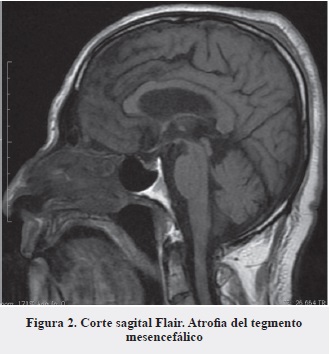

En nuestro caso la realización de la resonancia de cerebro constituyó una herramienta muy útil que, además de argumentar la sospecha clínica inicial, sirvió para descartar otras lesiones estructurales asociadas a caídas frecuentes (hematomas, hidrocefalia a presión normal, etc. ). Los hallazgos característicos de esta enfermedad son, principalmente, la atrofia del tegmento del mesencéfalo (Figura 2) en proyección sagital (signo del colibrí o del pingüino) (Figura 3) (16, 17), la alteración del diámetro anteroposterior y la atrofia generalizada del mesencéfalo (Figura 4) (18).